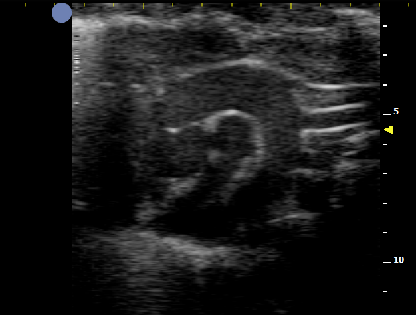

基于全球领先的CMUT半导体超声技术,集成70多项发明专利,珂纳医疗精心研发出SiliconWave系列超高频小动物超声成像系统。系统采用全“芯”一代数据采集平台,集成超高频专用AFE芯片,将图像的空间分辨率提升至30微米级高清成像。8-70MHz超宽频段的256多阵元超高频探头,丰富的软件测量包,便利的离线分析工作站和小动物专用操作平台,为科研用户开展小动物的心血管、腹部脏器、浅表组织及胚胎发育等实验模型的影像学观察和数据分析提供了极大的便利性。